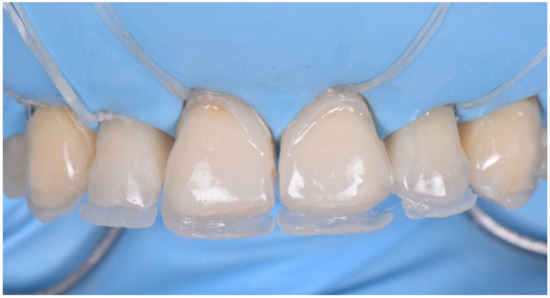

2.2. Restorative Phase